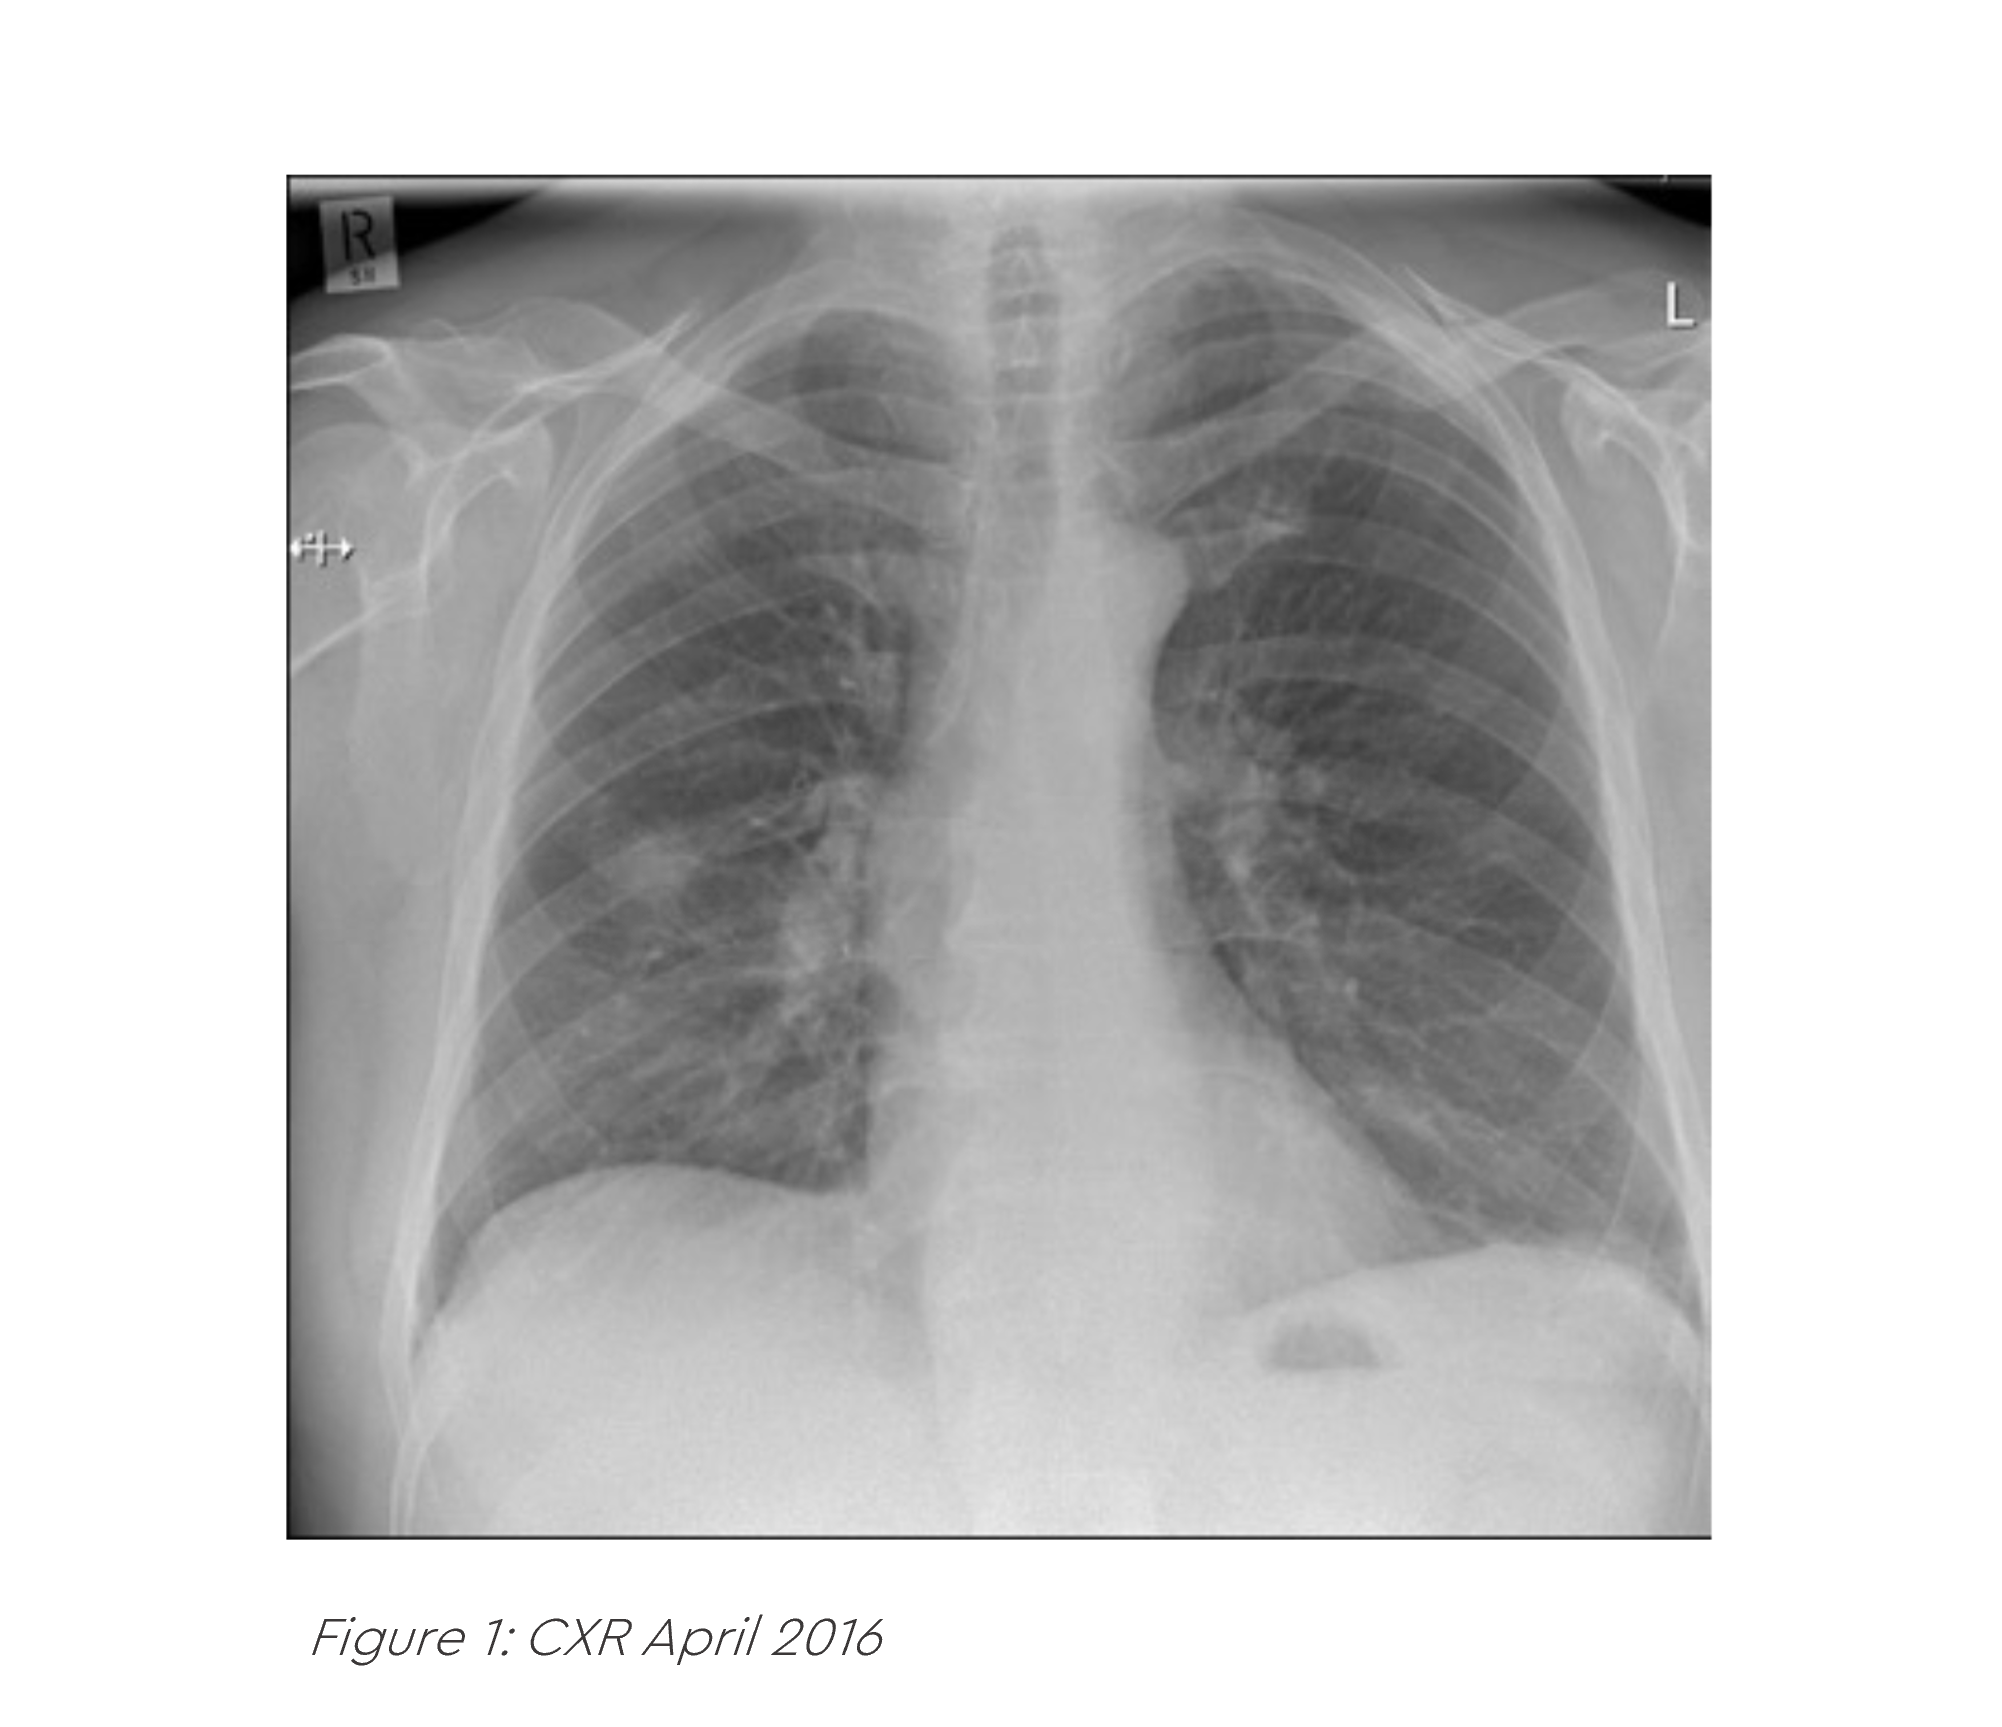

A 64-year-old gentleman presented to his GP in February 2016 with a persistent cough and new onset back pain. He was prescribed multiple courses of oral antibiotics, but his symptoms did not settle and a subsequent CXR in April 2016 was reported as abnormal. He was referred on a 2WW pathway to his local hospital where he had an urgent CT of his chest. This revealed a right lung mass, enlarged right hilar lymph nodes and a lytic metastasis in his T7 vertebra.

An EBUS was undertaken which confirmed an adenocarcinoma of the right lung. It was EGFR mutation negative and ALK fusion negative. A PET-CT scan confirmed his stage was T1b N1 M1b (solitary T7 met). An MRI scan of his brain was normal.